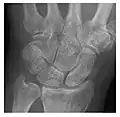

Figure 3: A 26-year-old man presenting with wrist pain after being assaulted. (a) Initial anteroposterior radiograph shows a subtle linear lucency within the scaphoid extending to the scaphocapitate articular surface that was overlooked (arrow). (b) Initial "scaphoid" view was negative. (c) Followup anteroposterior radiographs, 12 days later, shows obvious scaphoid fracture (arrows).[1]

Triquetral fracture usually occurs on the dorsal aspect by impingement from the ulnar styloid or avulsion of strong ligamentous attachment. The dorsal avulsion fracture or "chip fracture" appears as a small bony fragment on the dorsal aspect of the triquetrum and is best detected on the lateral view(Figure 4). When radiography is negative in patients with high suspicion of a fracture, both MRI and MDCT will be of value. However, it has been shown that MRI is superior for detecting trabecular fractures in carpal bones.

a

b

Figure 4: Dorsal triquetral fracture of the left wrist in a 30-year-old man after a trauma. (a) Anteroposterior radiograph shows a normal appearance. (b) Lateral radiograph of the same wrist demonstrates a chip fracture off the dorsal aspect of the triquetrum (arrow).[1]